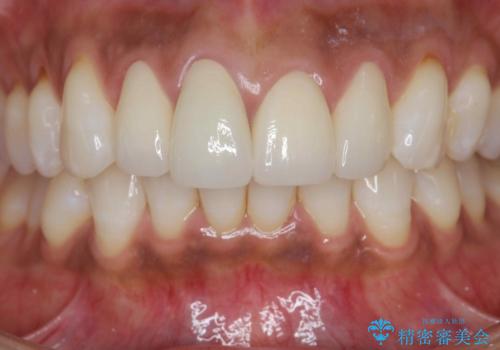

金属色の見える前歯 オールセラミックで審美治療

- 前歯のクラウンの見た目が不自然、歯の根元が見えたり金属色が気になるので改善したい、とセラミック治療を希望され来院されました。

歯肉の位置変化による審美障害を改善するため、オールセラミックジルコニアクラウンで再治療を行い審美性の改善を計画します。

見た目が自然になり、色調も天然の歯とおなじような透明感のある色調が再現され、大変喜んでいただくことができました。